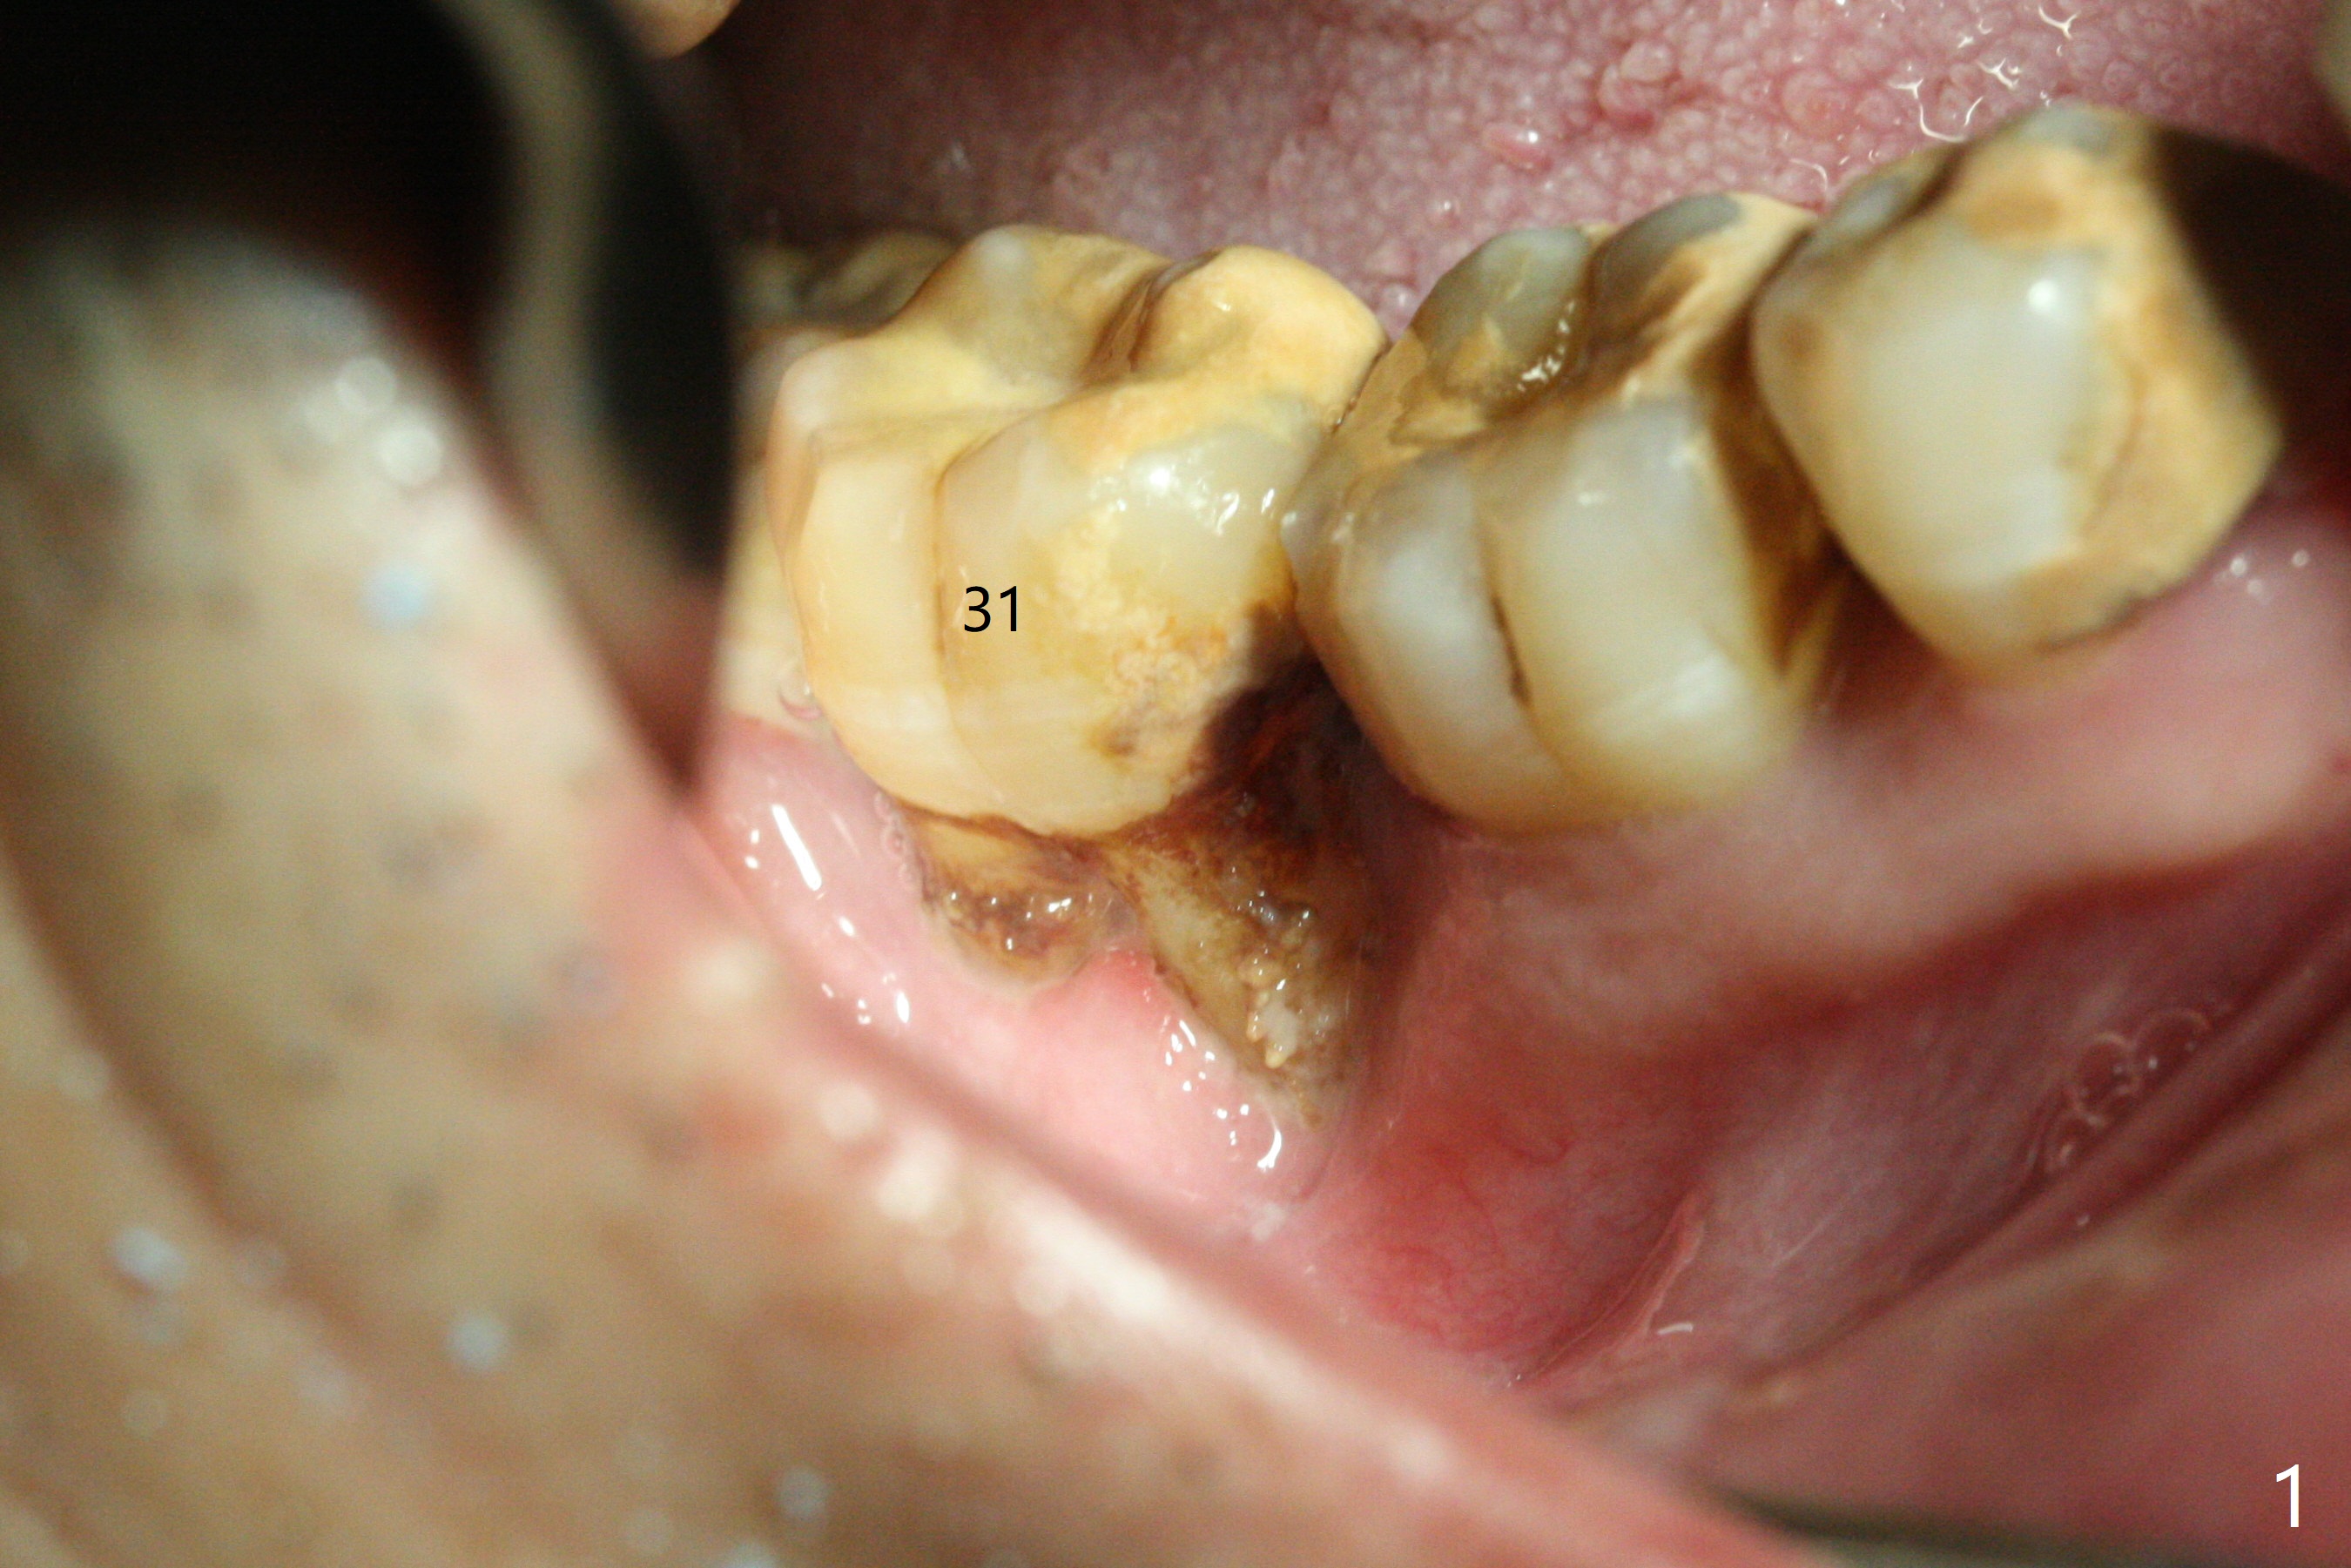

The affected tooth (#31, Fig.1) has severe buccal gingival recession with mobility III. After extraction and removal of granulation tissue, osteotomy is initiated in the middle of the fused socket using IS drills with 4 mm stopper (Fig.2,3). Following sequential osteotomy until 4 mm drill, a 4.5x10 mm IS dummy implant does not achieve primary stability, whereas 5x10 mm one does (Fig.4,5). Due to limited bone height confirmed intraoperatively, a shorter UF implant is placed with insertion torque 30 Ncm (Fig.6,7) with ~ 4.5 mm implant threads exposed coronally. After placing a 6.5x5(5) mm abutment, Vanilla Graft (*) and PRF membrane and collagen plug, an immediate provisional is fabricated to close the remaining socket. The tooth #32 is kept initially to increase the stability of the provisional and removed 8 day postop because of discomfort. A 5.5(2.5) mm mill abutment is changed to 3 months postop. The implant seems ready for impression 6 months postop (Fig.8). The bone graft remains around the apical portion of the mill abutment with apparently new bone formation around the coronal portion of the implant10 months postop (Fig.9); porcelain (*) has been added to close the mesial gingival embrasure and proximal contact gap. Due to unfavorable crown/implant ratio and poor trajectory, the crown/abutment becomes loose once post 1st cementation. Guided surgery would avoid the trajectory isssue.